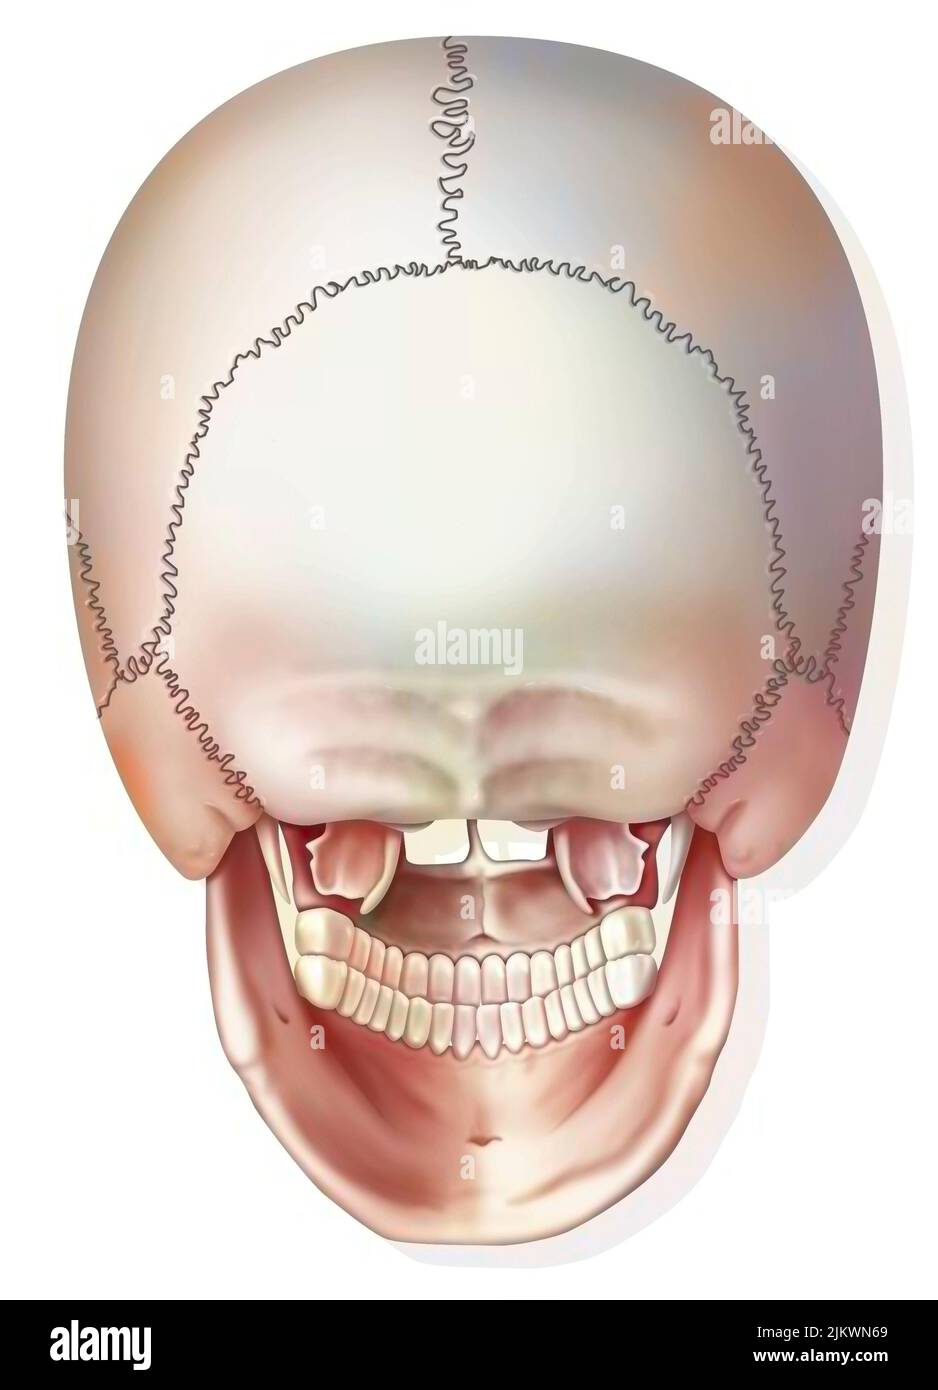

Vue postérieure des os du crâne et de la mâchoire. Banque D'Imageshttps://www.alamyimages.fr/image-license-details/?v=1https://www.alamyimages.fr/vue-posterieure-des-os-du-crane-et-de-la-machoire-image476923894.html

Vue postérieure des os du crâne et de la mâchoire. Banque D'Imageshttps://www.alamyimages.fr/image-license-details/?v=1https://www.alamyimages.fr/vue-posterieure-des-os-du-crane-et-de-la-machoire-image476923894.htmlRF2JKWN86–Vue postérieure des os du crâne et de la mâchoire.

Vue postérieure des os du crâne et de la mâchoire. Banque D'Imageshttps://www.alamyimages.fr/image-license-details/?v=1https://www.alamyimages.fr/vue-posterieure-des-os-du-crane-et-de-la-machoire-image476923841.html

Vue postérieure des os du crâne et de la mâchoire. Banque D'Imageshttps://www.alamyimages.fr/image-license-details/?v=1https://www.alamyimages.fr/vue-posterieure-des-os-du-crane-et-de-la-machoire-image476923841.htmlRF2JKWN69–Vue postérieure des os du crâne et de la mâchoire.